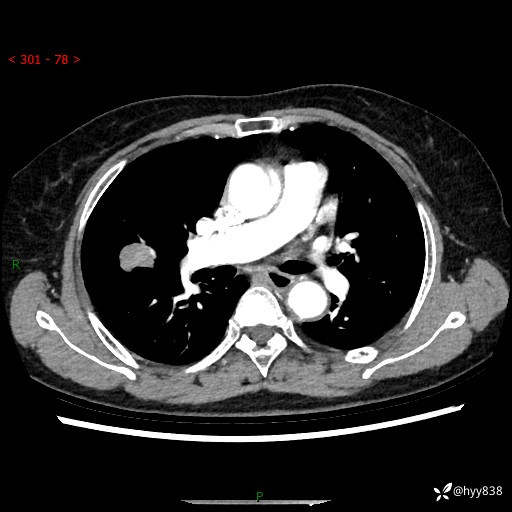

胸部CT平扫+增强